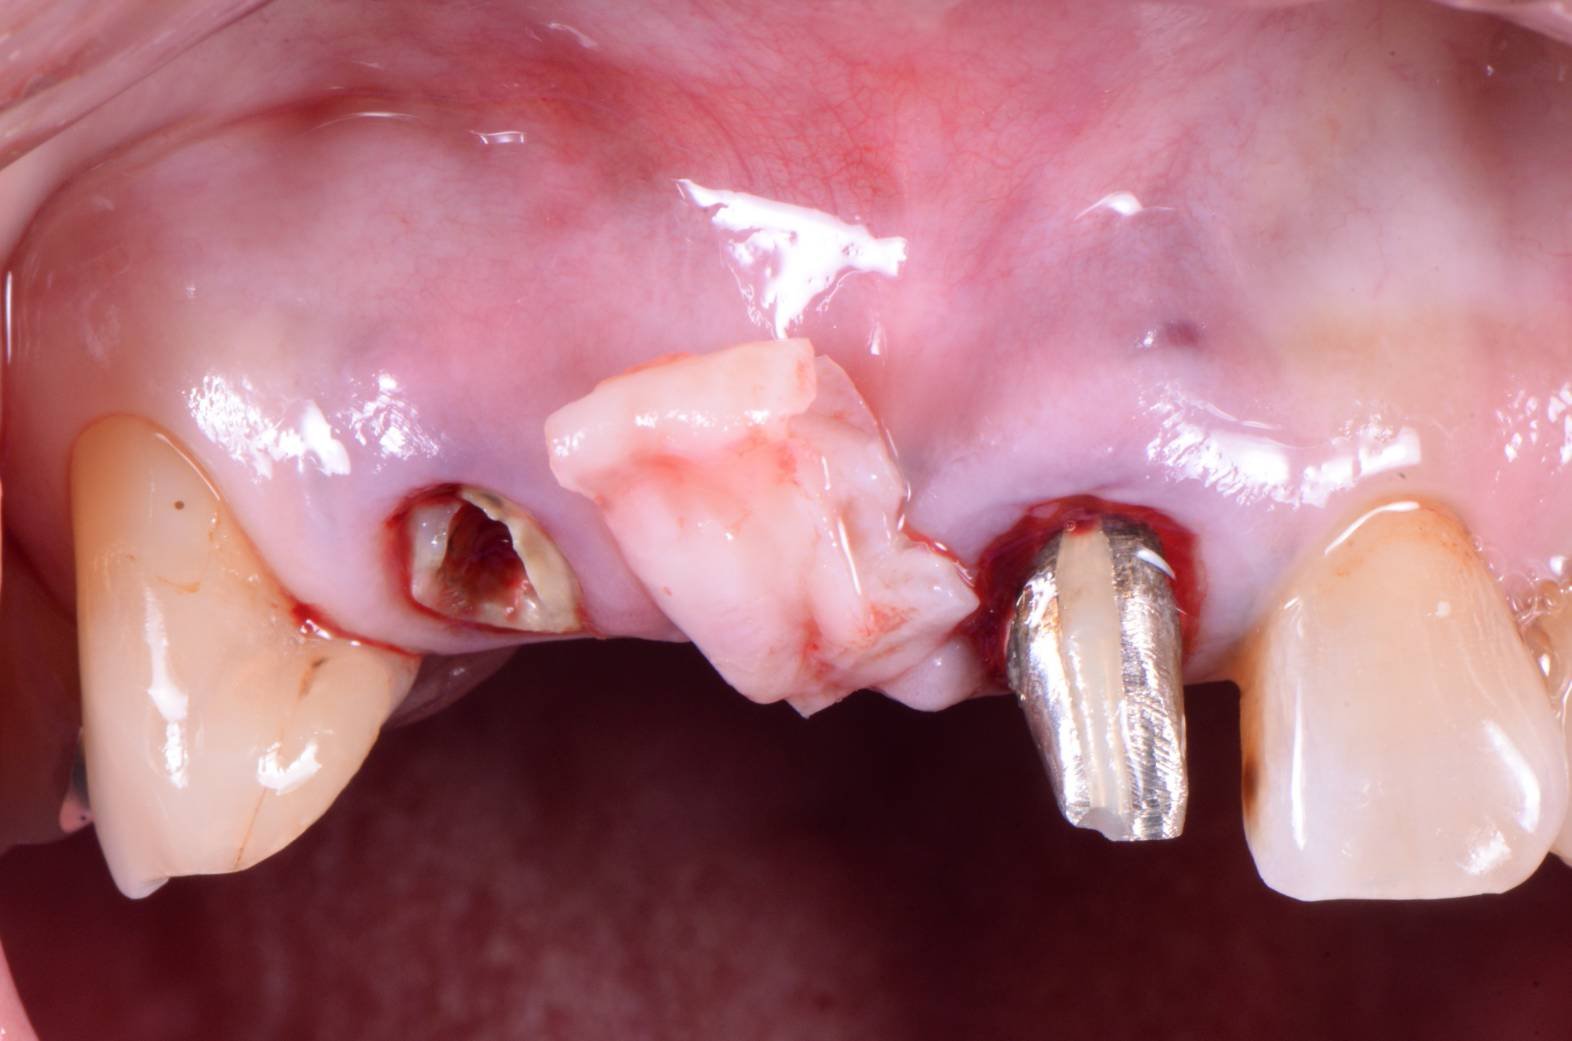

さらにこのオベイドポンティックを造るためには、歯肉の移植も必要なのです。↓の写真